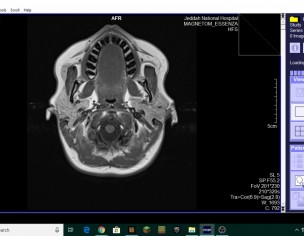

Had difficulty in swallowing and continuous sore throat, then noticed a thickening of lining inside and behind upper third molar. Had gap in front teeth which has decreased. Had a filling and root canal for two teeth on two teeth on upper right. Have an opg before the root canal. The swelling is hard and painless and appears to be normal mucosa to the dentist I visited but I am worried as it seems to be increasing gradually. can it be checked by looking only? Had an MRI done for severa pain in head, some parts show upper jaw. Attaching. Please advise.

Attach Photo here: